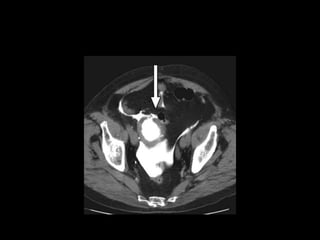

Diagnostico

• Estudio elección: cistograma de llenado 350-

400ml solución salina, con 4% de contraste a

una altura de infusión de 40 cm.

• Cystography: Gold standard

• CT Cystography : New trend

• Peng et al. AJR 2011.

– Prospective study

– 305 patients.

– Cystography VS. CT cystography

– Ruptures confirmed by Surgery

– 100% sensitive and specific